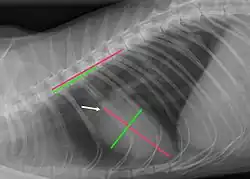

Der VHS wird zumeist anhand einer Röntgenaufnahme des Brustkorbs in Seitenlage bestimmt. Auf dem Röntgenbild werden die Strecke von der Aufzweigung der Luftröhre zur Herzspitze sowie eine rechtwinklig dazu verlaufende Strecke an der breitesten Stelle des Herzens ermittelt.[1][2] Für Hunde mit einer starken Vergrößerung des linken Vorhofs schlägt Buchanan vor, das obere Ende der Längsachse am angehobenen linken Bronchus anzusetzen. Bei älteren Katzen, bei denen die lange Herzachse oft fast parallel zum Brustbein verläuft, wird statt der Luftröhrenaufzweigung die Basis der Vene des vorderen Lungenlappens als Messpunkt empfohlen. Die Vermessung der Herzachsen kann auch auf einer Röntgenaufnahme in Rückenlage erfolgen.[3] Allerdings ist beim Hund bei dieser Projektion der linke Vorhof nicht an der Bildung der Herzsilhouette beteiligt.[4]

Die beiden Strecken werden auf die Brustwirbelsäule, beginnend jeweils am Vorderende des vierten Brustwirbelkörpers, übertragen. Anschließend wird die Anzahl der Wirbel bestimmt, die diese Strecken einnehmen. Wenn das Ende der Strecke keinen ganzen Wirbel mehr umfasst, wird dieser Teilwirbel auf ein Zehntel genau ermittelt: Reicht also beispielsweise die Länge der Längsachse vom Anfang des vierten bis zur Mitte des neunten Brustwirbels, so beträgt der Wert für diese Strecke 5,5.[1][2] Die Länge eines Wirbelkörpers zusammen mit der zugehörigen Bandscheibe dient dabei als ein die Größe des Individuums reflektierendes, relatives Längenmaß. Da die Wirbelkörperlängen innerhalb der Wirbelsäule variieren, ist es von Bedeutung, stets mit einem definierten Wirbel zu beginnen. Der in der Humanmedizin zur Größenbeurteilung des Herzens herangezogene Herz-Thorax-Quotient ist bei Hunden wegen der großen Rasseunterschiede in der Brustkorbform nicht geeignet.

Der Vertebral Heart Score ist die Summe der Wirbel, die Längs- und Querachse einnehmen. Ein VHS bis 10,5 (Hund) bzw. 8,1 (Katze) gilt als normal, höhere Werte sprechen für eine Herzvergrößerung (Kardiomegalie).[5] Für das Erkennen einer Herzverkleinerung (Mikrokardie) wird der VHS nicht herangezogen. Dafür wird die Anzahl der Zwischenrippenräume bestimmt, über die die Herzsilhouette reicht. Eine Herzverkleinerung ist in der Regel nicht durch eine Herzerkrankung, sondern durch einen Blutvolumenmangel bedingt. Das Herz nimmt dabei weniger als zwei Zwischenrippenräume ein.[6]